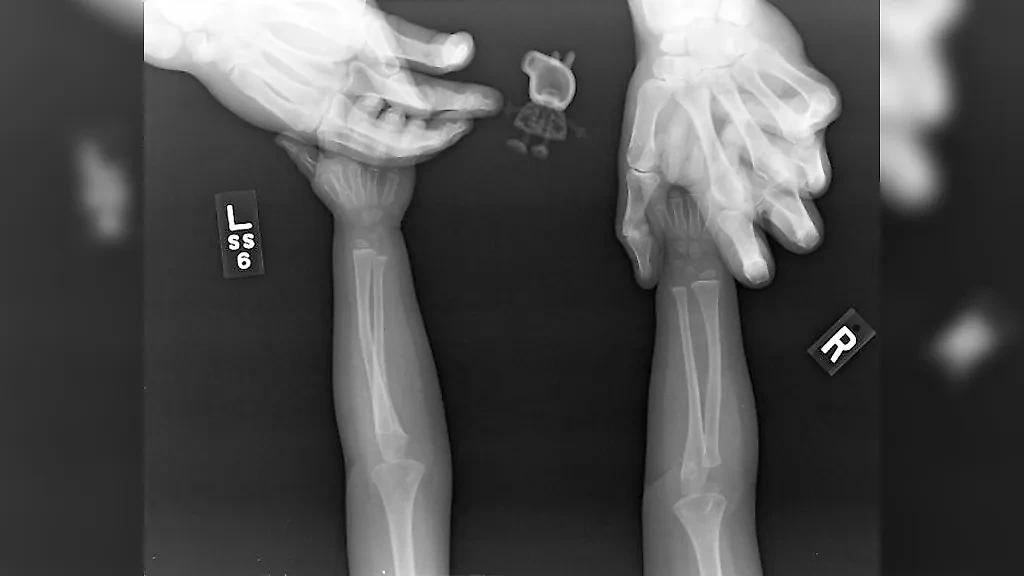

"Дочь взяла свою игрушку Свинку Пеппу на рентген", — cynicalslacker.

Фото © Reddit / cynicalslacker